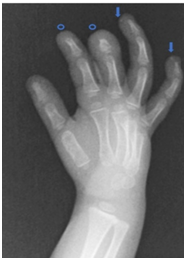

A four-month-old female was referred to the Dermatology department for the evaluation of asymptomatic white lesions of stony consistency on the fingertip of the fourth and fifth finger of her right hand, dermoscopy showed round homogeneous white images with hyperkeratotic collar (Figure 1). The patient was born preterm at 26 weeks gestation, presenting with hyaline membrane disease, bronchopulmonary dysplasia and mild pulmonary hypertension. During admission, she developed ischemia of digital arteries in the right hand, due to thromboembolism secondary to the manipulation of an epicutaneous catheter in the right axillary artery. The patient required amputation of the distal phalanx of the second finger as well as distal and half of the middle phalanx of the third finger, two months later, lesions on the fingertips started to appear. The results of the routine complementary tests were normal except for elevated alkaline phosphatase values (2492 IU/L) without other alterations of phosphocalcic metabolism. These values normalized after one month, meeting the diagnostic criteria of benign transient childhood hyperphosphatemia.4 An X-ray of the right hand was also performed, showing hyperdense round images on the palm side of the 4th and 5th fingers suggestive of calcifications (Figure 2 ), as well as the amputated phalanges (Figure 2 •). Under local anesthesia, because the lesions were predominantly detached, curettage was performed on the remaining areas. Histology showed granules and globules of basophilic calcified material (Figure 3 ★) and foreign body giant cell reaction in dermis (Figure 3 ▲).

Figure 2 Right hand radiography. Hyperdense round images are observed on the palmar side of the 4th and 5th fingers suggestive of calcifications (). Also, amputation of the distal phalanx of the 2nd finger as well as distal and half of the middle phalanx of the 3rd finger of the right hand (•).